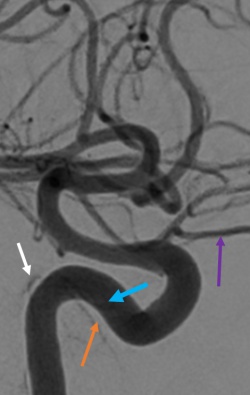

DSA: DSA remains the gold standard imaging modality in the diagnosis of direct and indirect CCFs. DSA is necessary to identify CCF location, arterial supply, flow rate, and venous drainage to classify the CCF and help plan for potential endovascular treatment strategies.[24][28]

Endovascular treatment of indirect CCFs is primarily via a transvenous route unlike treatment of direct CCF.[35][39] Transarterial embolization is often primarily attempted via the femoral artery. Occasionally fistulous connection from dural branches the ICA limits the transarterial approach due to the risk of stroke and arterial dissection with treatment. When anatomic variations limit transarterial access, transvenous embolization may be attempted via the petrosal sinuses and pterygoid plexus. Additionally, an orbital surgeon may be asked to expose the superior ophthalmic vein via an anterior orbitotomy for direct canulation.[40][41] Embolization proceeds with detachable coils or liquid embolics (Onyx, n-BCA) to obliterate the fistula, restore normal orbital venous drainage and preserve intradural arterial flow. During transvenous embolization, the arterial circulation is monitored with intermittent angiography via the ipsilateral ICA to ensure the patency of normal cerebral vasculature.